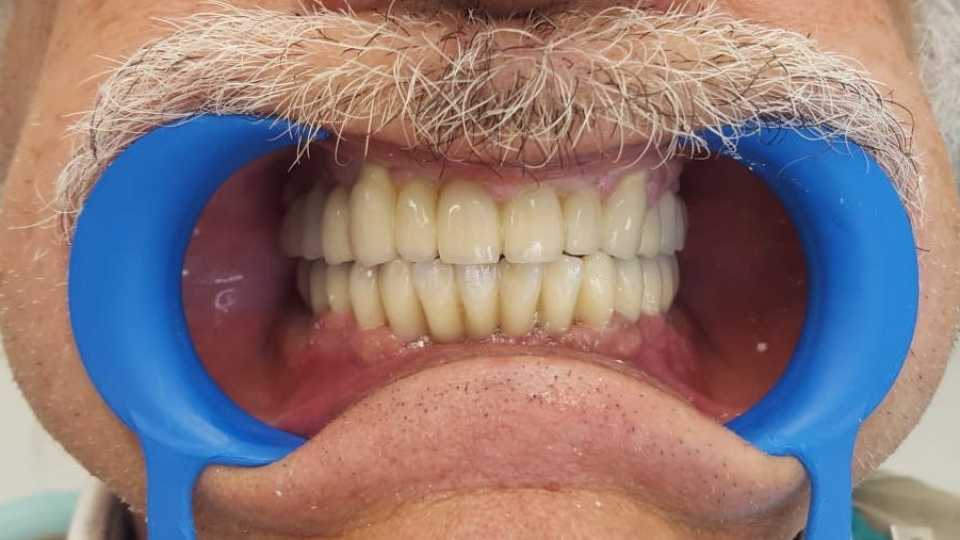

Pacient in varsta de 67 de ani, cunoscut cu boala parodontala severa cu mobilitate avansata a tuturor dintilor, care se prezinta in cadrul clinicii noastre atat din motive functionale, cat si estetice.

Acesta a optat pentru extractia dintilor afectati si protezarea fixa cu ajutorul implanturilor dentare, pacientul dorind respectarea formei si a culorii danturii proprii. Avand in vedere pierderea osoasa importanta, cauzata de patologia pacientului, acesta a necesitat in vederea reabilitarii, atat de sinus lift extern, cat si de aditie osoasa cu os artificial si membrana de colagen.

S-au inserat 10 implanturi dentare la nivel maxilar si 7 la nivel mandibular, pe baza carora s-au realizat protezari fixe metalo-cermice mandibular si ceramica pe zirconiu la nivel maxilar.